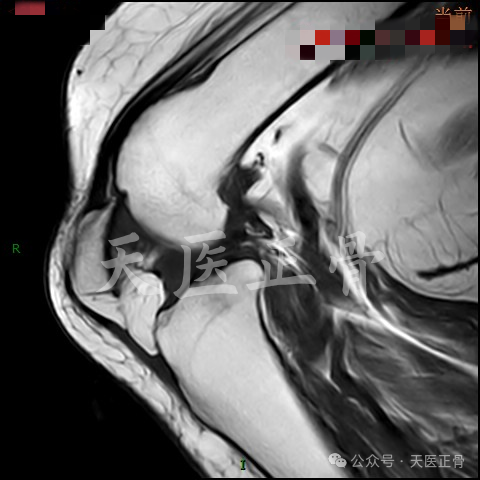

膝关节矢状位MR图像

图片

根据本例MR的图像可以证实髌骨上极骨赘嵌顿于髁间窝导致髌骨关节内嵌顿的假设,从而引起髌骨关节内水平脱位。